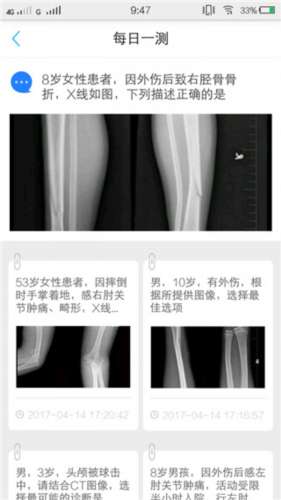

点击题库王可以进行在线刷题学习